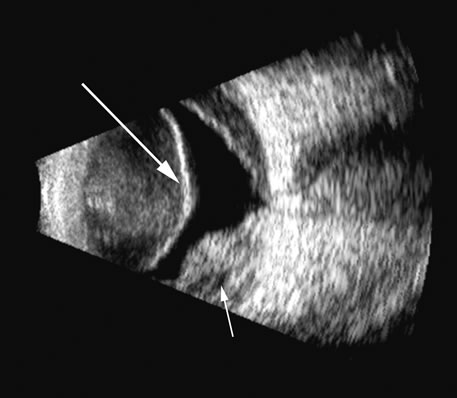

Fig. 17. This patient with a Molteno tube was treated for glaucoma. The top 50 MHz B-scan clearly shows the Molteno Tube (arrow). The bottom 10 MHz B-scan of the same patient demonstrates a choroidal detachment (large arrow) with associated posterior retinal detachment (small arrow). Choroidal elevations are typically convex, highly reflective surfaces with posterior limitation at the vortex vessels. Retina will always attach at the optic nerve. Choroidal elevations are often noted in several quadrants, as seen here.